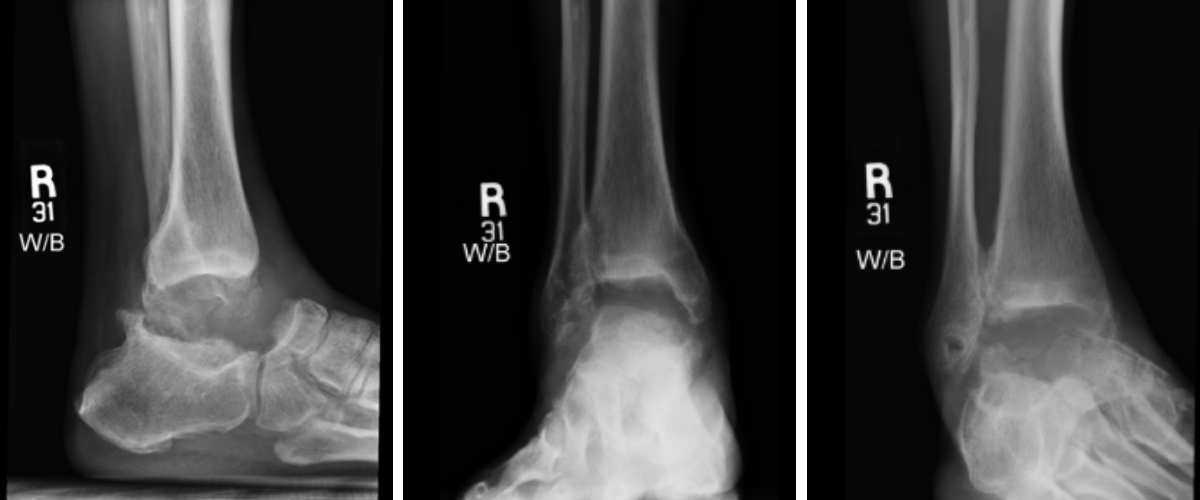

Preoperative plain film imaging demonstrated intact hardware with slight lateral deviation, implant tilt, medial tibiotalar joint space narrowing, varus deformity, and degenerative changes in both the tibiotalar and subtalar joints (Figure 1). Computed tomography (CT) confirmed subchondral sclerosis and erosive changes along the tibial plafond and subtalar articular surface (Figure 2). In addition, CT imaging of the contralateral ankle guided preoperative planning and informed patient-specific implant design. A 3D model with prototype images assisted with preoperative planning (Figure 3). The final implant was manufactured from 3D-printed PEKK by Oxford Performance Materials (OPM).